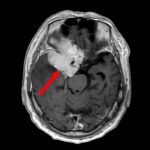

症例 '17年1月

No.

9

※ 画像をクリックすると拡大表示します。症例No.は平成29年から起算しています。

年_番号

手術年月

患者年齢

’17_9

'17年1月

70代

病名

術式

備考

蝶形骨稜髄膜腫

頭蓋内腫瘍摘出術

断層撮影

手術前

1

手術前2

手術後